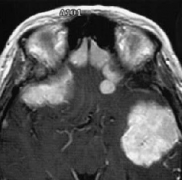

脑膜瘤严重吗?不足9%的颅内脑膜瘤位于后颅窝。Olivercrona等报道了4185例脑肿瘤,颅内脑膜瘤为803例,有68例位于后颅窝(包括20例小脑幕脑膜瘤)。由于后颜窝的...